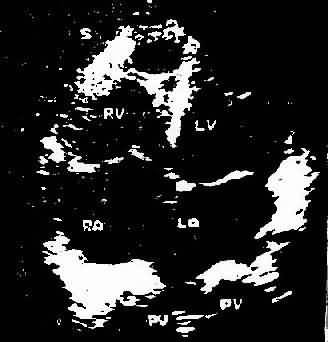

此是利用超声扫描技术 在荧光屏上显示超声波通过心脏各层结构如;心包、心肌、心内膜、室间隔、瓣膜和主动脉时发生的反射,借以观察心脏与大血管的搏动情况、房室的舒张和瓣膜开关的活动规律。目前常用的M型、B型超声心动图对二尖瓣、主动脉瓣的狭窄和关闭不全、三尖瓣狭窄,二尖瓣脱垂,特发性肥厚性主动脉瓣下狭窄,心房粘液瘤,心包积液,房、室间隔缺损等的诊断均有较大的价值。此外,利用超声心动图测量房、室腔的大小,计算心排出量、射血分数等以了解左心室功能。近年来应用彩色多普勒血流显像探查瓣膜关闭不全的返流和先心病的分流量、提高了疾病诊断质量。(图3-1-4图3-1-5)

图3-1-5 心尖四腔心切面二维超声心动图

A、照片 B、示意图